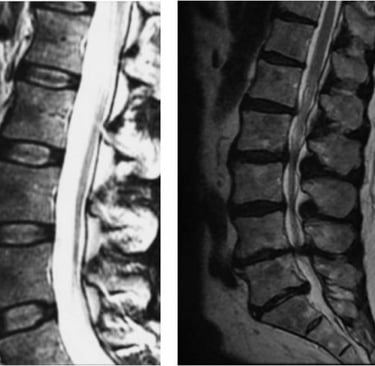

A coluna vertebral é formada por uma sequência de vértebras organizadas em regiões: cervical, torácica e lombar. Entre essas vértebras estão os discos intervertebrais, que atuam como amortecedores, absorvendo impactos e permitindo movimentos com flexibilidade.

Hérnia de disco

Estenose do canal lombar